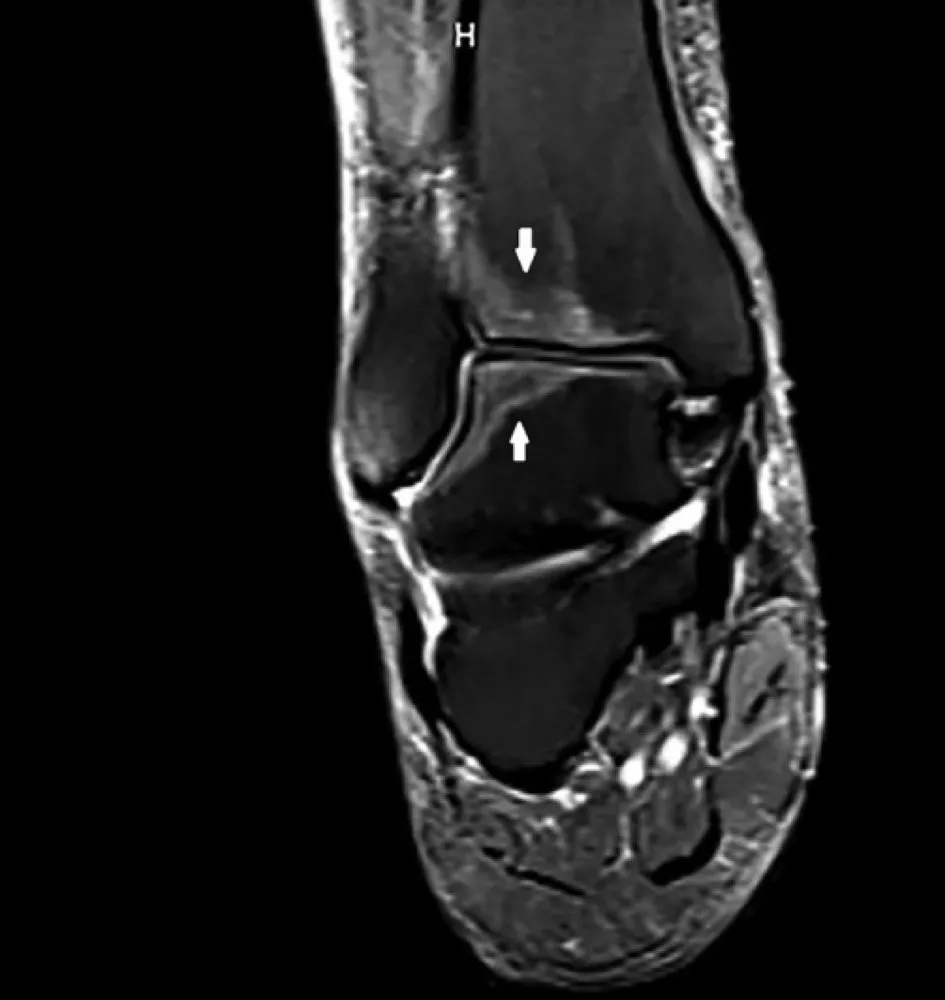

DRC indeterminada ou você esqueceu de fazer o básico? Veja tudo aqui

DRC “indeterminada” raramente é falta de diagnóstico — quase sempre é falta de método. Tempo de evolução, urina bem avaliada, USG renal e história clínica dirigida mudam conduta e evitam erros comuns na prática nefrológica.